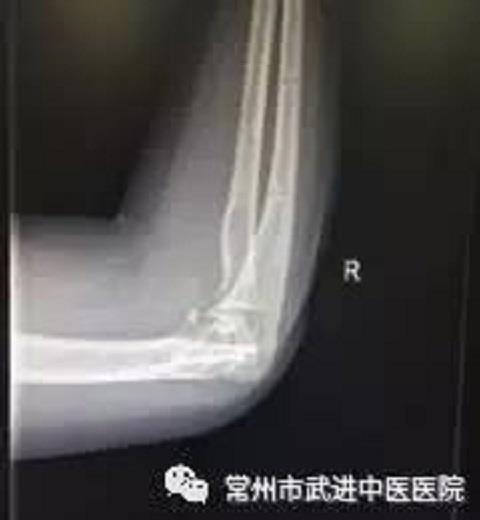

王女士以为拆掉外固定后肘关节活动就自如了,没想到患处仍肿胀疼痛,关节活动受限,穿衣,吃饭等日常活动均受影响。无奈之下,她一脸愁容地来到武进中医医院康复分院寻求解决办法。

外固定拆除后DR片(下) 王女士住院后,康复医生做了详细的功能评定。